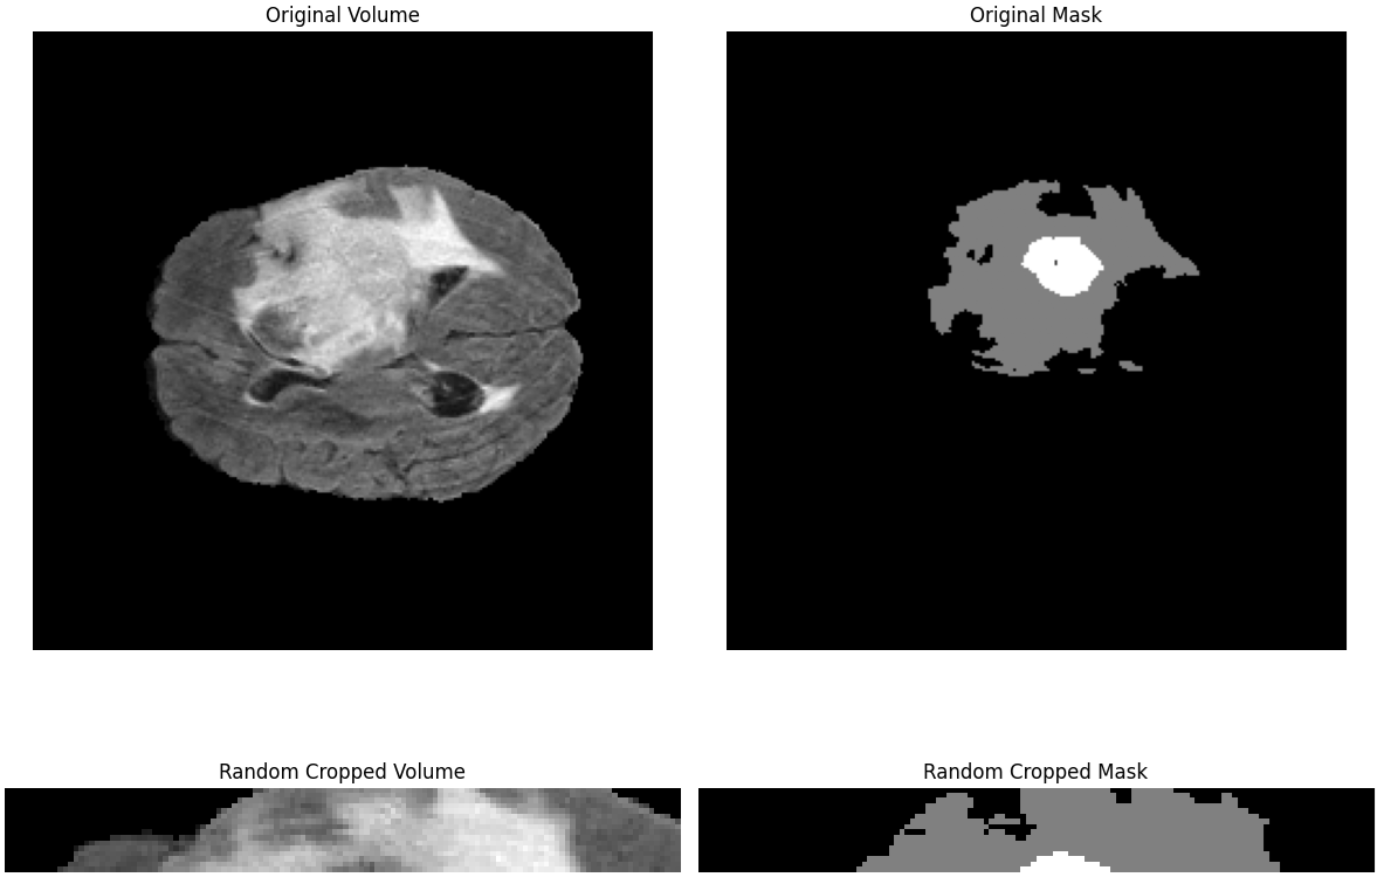

RandomCrop3D: Randomly crops a sub-volume of the specified (depth, height, width) from a 3D image. If the original volume is smaller than the crop size, it can optionally pad the volume before cropping.

Key parameters used are:

size (tuple[int, int, int]): The output crop size specified as (depth, height, width).pad_if_needed(bool): Default isFalse, if set to True, the volume will be padded (using fill or fill_mask) when it's smaller than the requested crop size.fill(float or tuple): Default0, the value used to pad the image if needed.fill_mask(float or tuple): Default is0, the value used to pad the mask if needed.p(float): Default is1.0, the probability that this transform will be applied.

# Load 3D volume and mask

volume = nib.load("BraTS20_Training_001_flair.nii").get_fdata().astype(np.float32)

mask = nib.load("BraTS20_Training_001_seg.nii").get_fdata().astype(np.uint8)

# Define transform

transform = A.RandomCrop3D(

size=(16, 128, 128),

pad_if_needed=True,

fill=0,

fill_mask=0,

p=1.0

)

# Apply transform

augmented = transform(volume=volume, mask3d=mask)

vol_aug = augmented["volume"]

mask_aug = augmented["mask3d"]

Output will be similar to following.